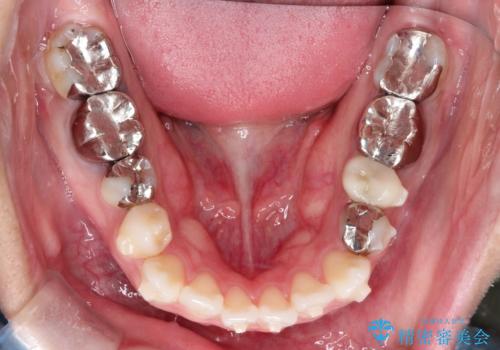

インビザラインで目立たない矯正 ガタガタの歯並びをきれいな歯並びへ

- 全体的なガタガタが気になるとのことで来院されました。

歯と歯のあいだをわずかに削りスペースを作り、ガタガタを改善する計画としました。